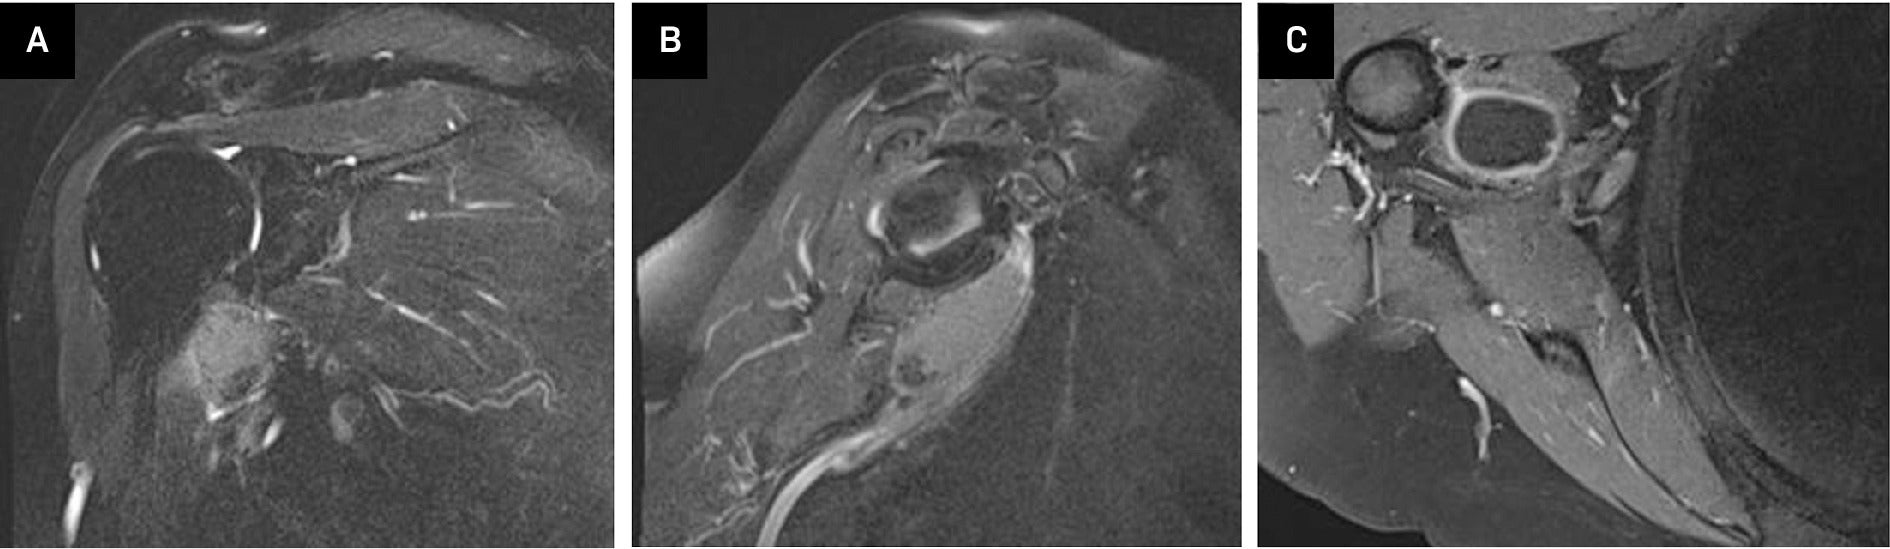

Calcific Subcoracoid Bursitis